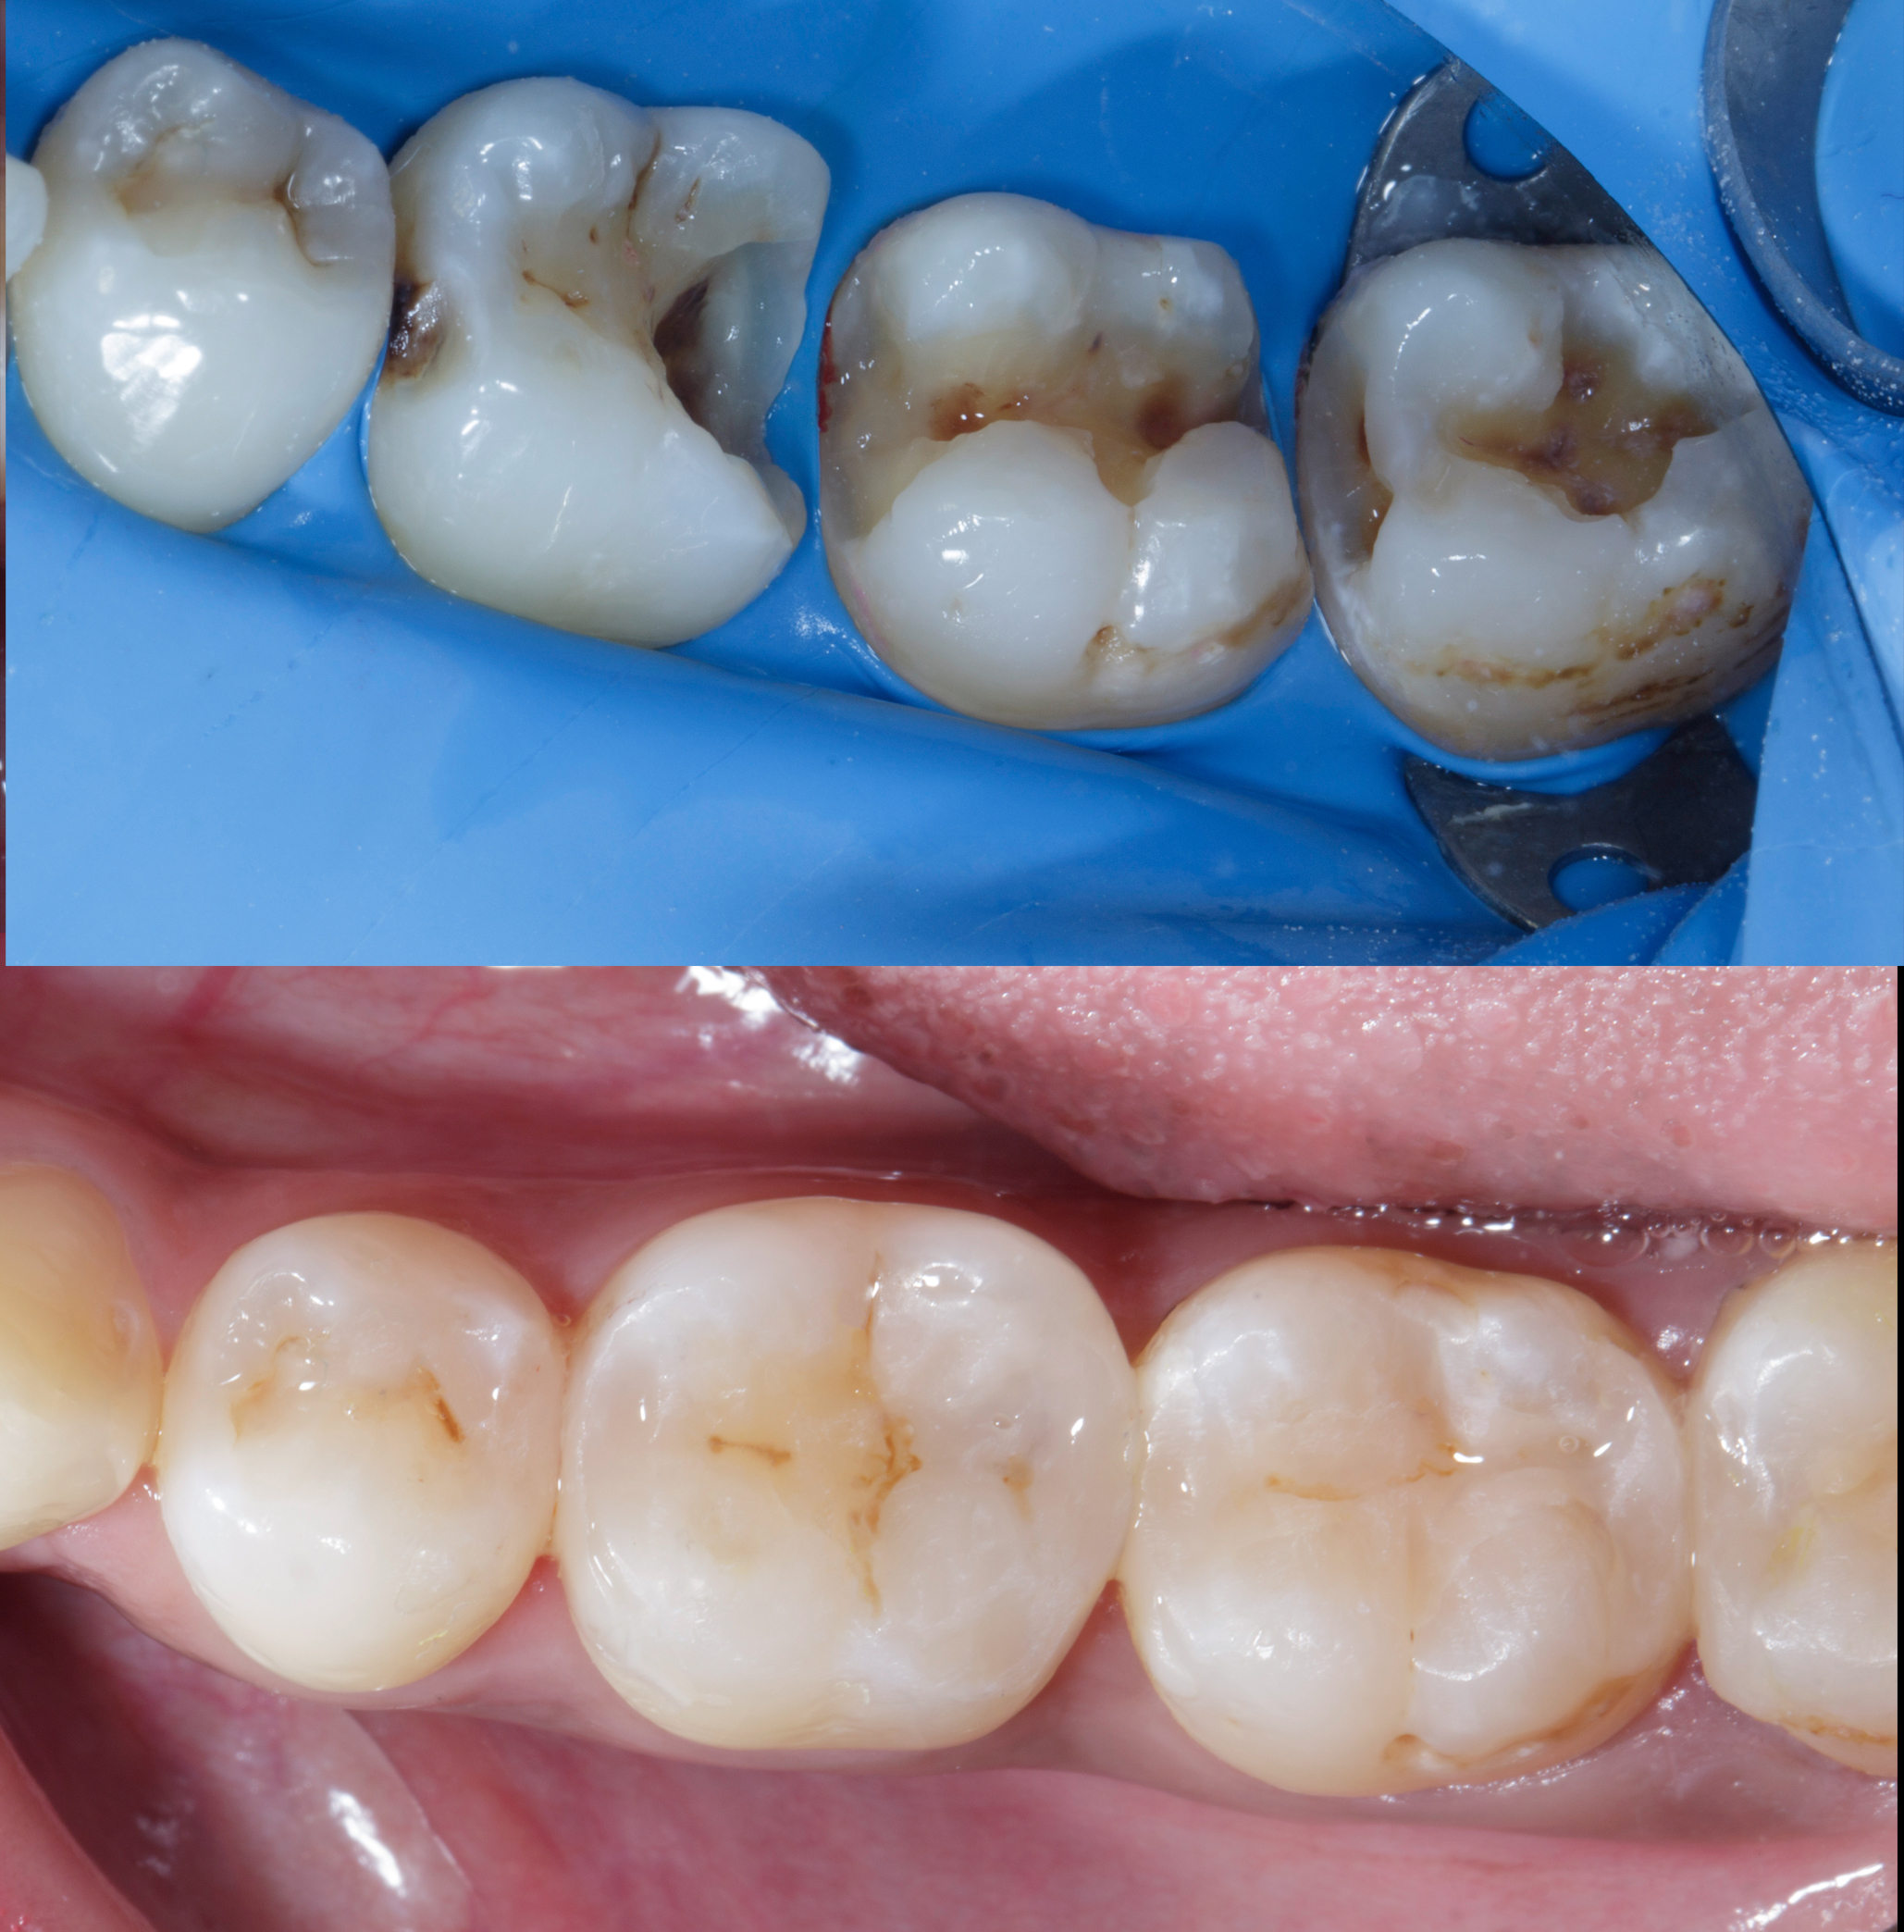

Figure 1

Figure 2

Figure 1. Multiple defects starting from tooth #45 to #48 as described above.Figure 2. Multiple class 2 defects starting from tooth #45 to #48 with loss of ideal contacts and contours.